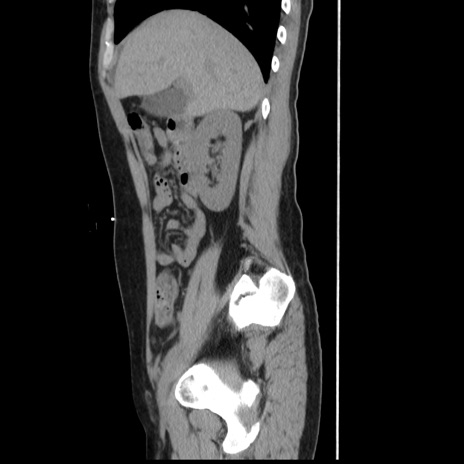

症例10(矢状断像)

【症例】 50歳代女性

【主訴】 腹痛

【現病歴】前日生レバーを食べた。今朝に排便あり。 昼前に突然発症の腹痛を生じ、当院救急外来を受診した。

【既往歴】 子宮筋腫にてで子宮全摘後

【身体所見】 意識清明、腹部:平坦、軟、下腹部やや左を中心に圧痛・反跳痛あり、筋性防御あり

【データ】WBC 7800、CRP 0.07